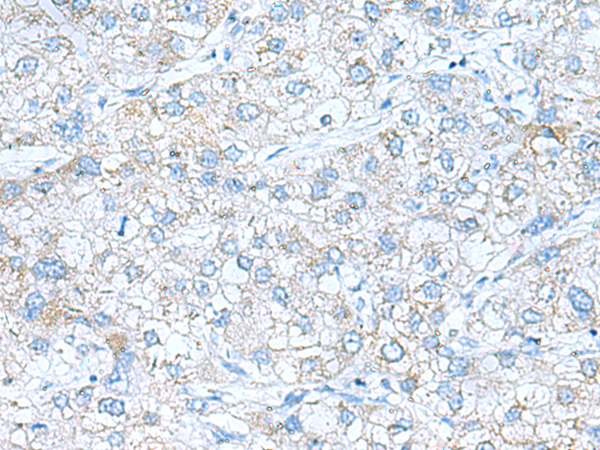

分类: 科研抗体货号: P11602别名: VGR; VGR1应用: IHC反应种属: Human, Rat